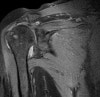

- MRI

견봉쇄골관절염 자체만으로 MRI 촬영의 필요성은 크지 않습니다.

아래와 같은 증상을 보입니다.

a. 골수부종

b. 관절낭 비후

c. 관절낭 주위 부종

d. 관련 부위의 견봉하 점액낭염, 회저근개와 주위 골극과의 충돌

MRI : 견봉쇄골관절염(견쇄관절염, Acromio-clavicular arthritis)